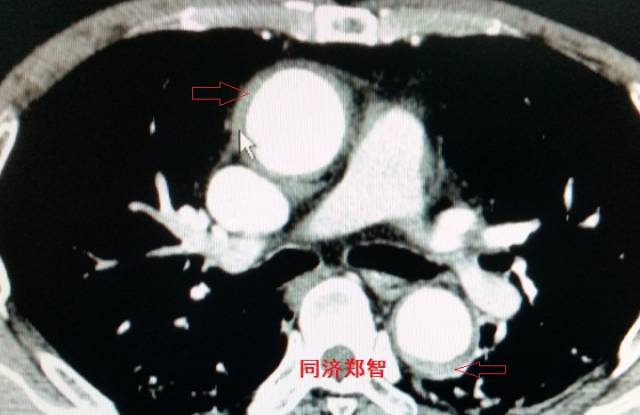

胸部平扫CT提示升主动脉增宽(红色星形标记),CTA证实A型主动脉夹层伴升主动脉夹层动脉瘤形成。

病例三

胸部平扫CT提示胸降动脉增宽(红色星形标记),CTA证实B型主动脉夹层伴降主动脉夹层动脉瘤形成。

病例四